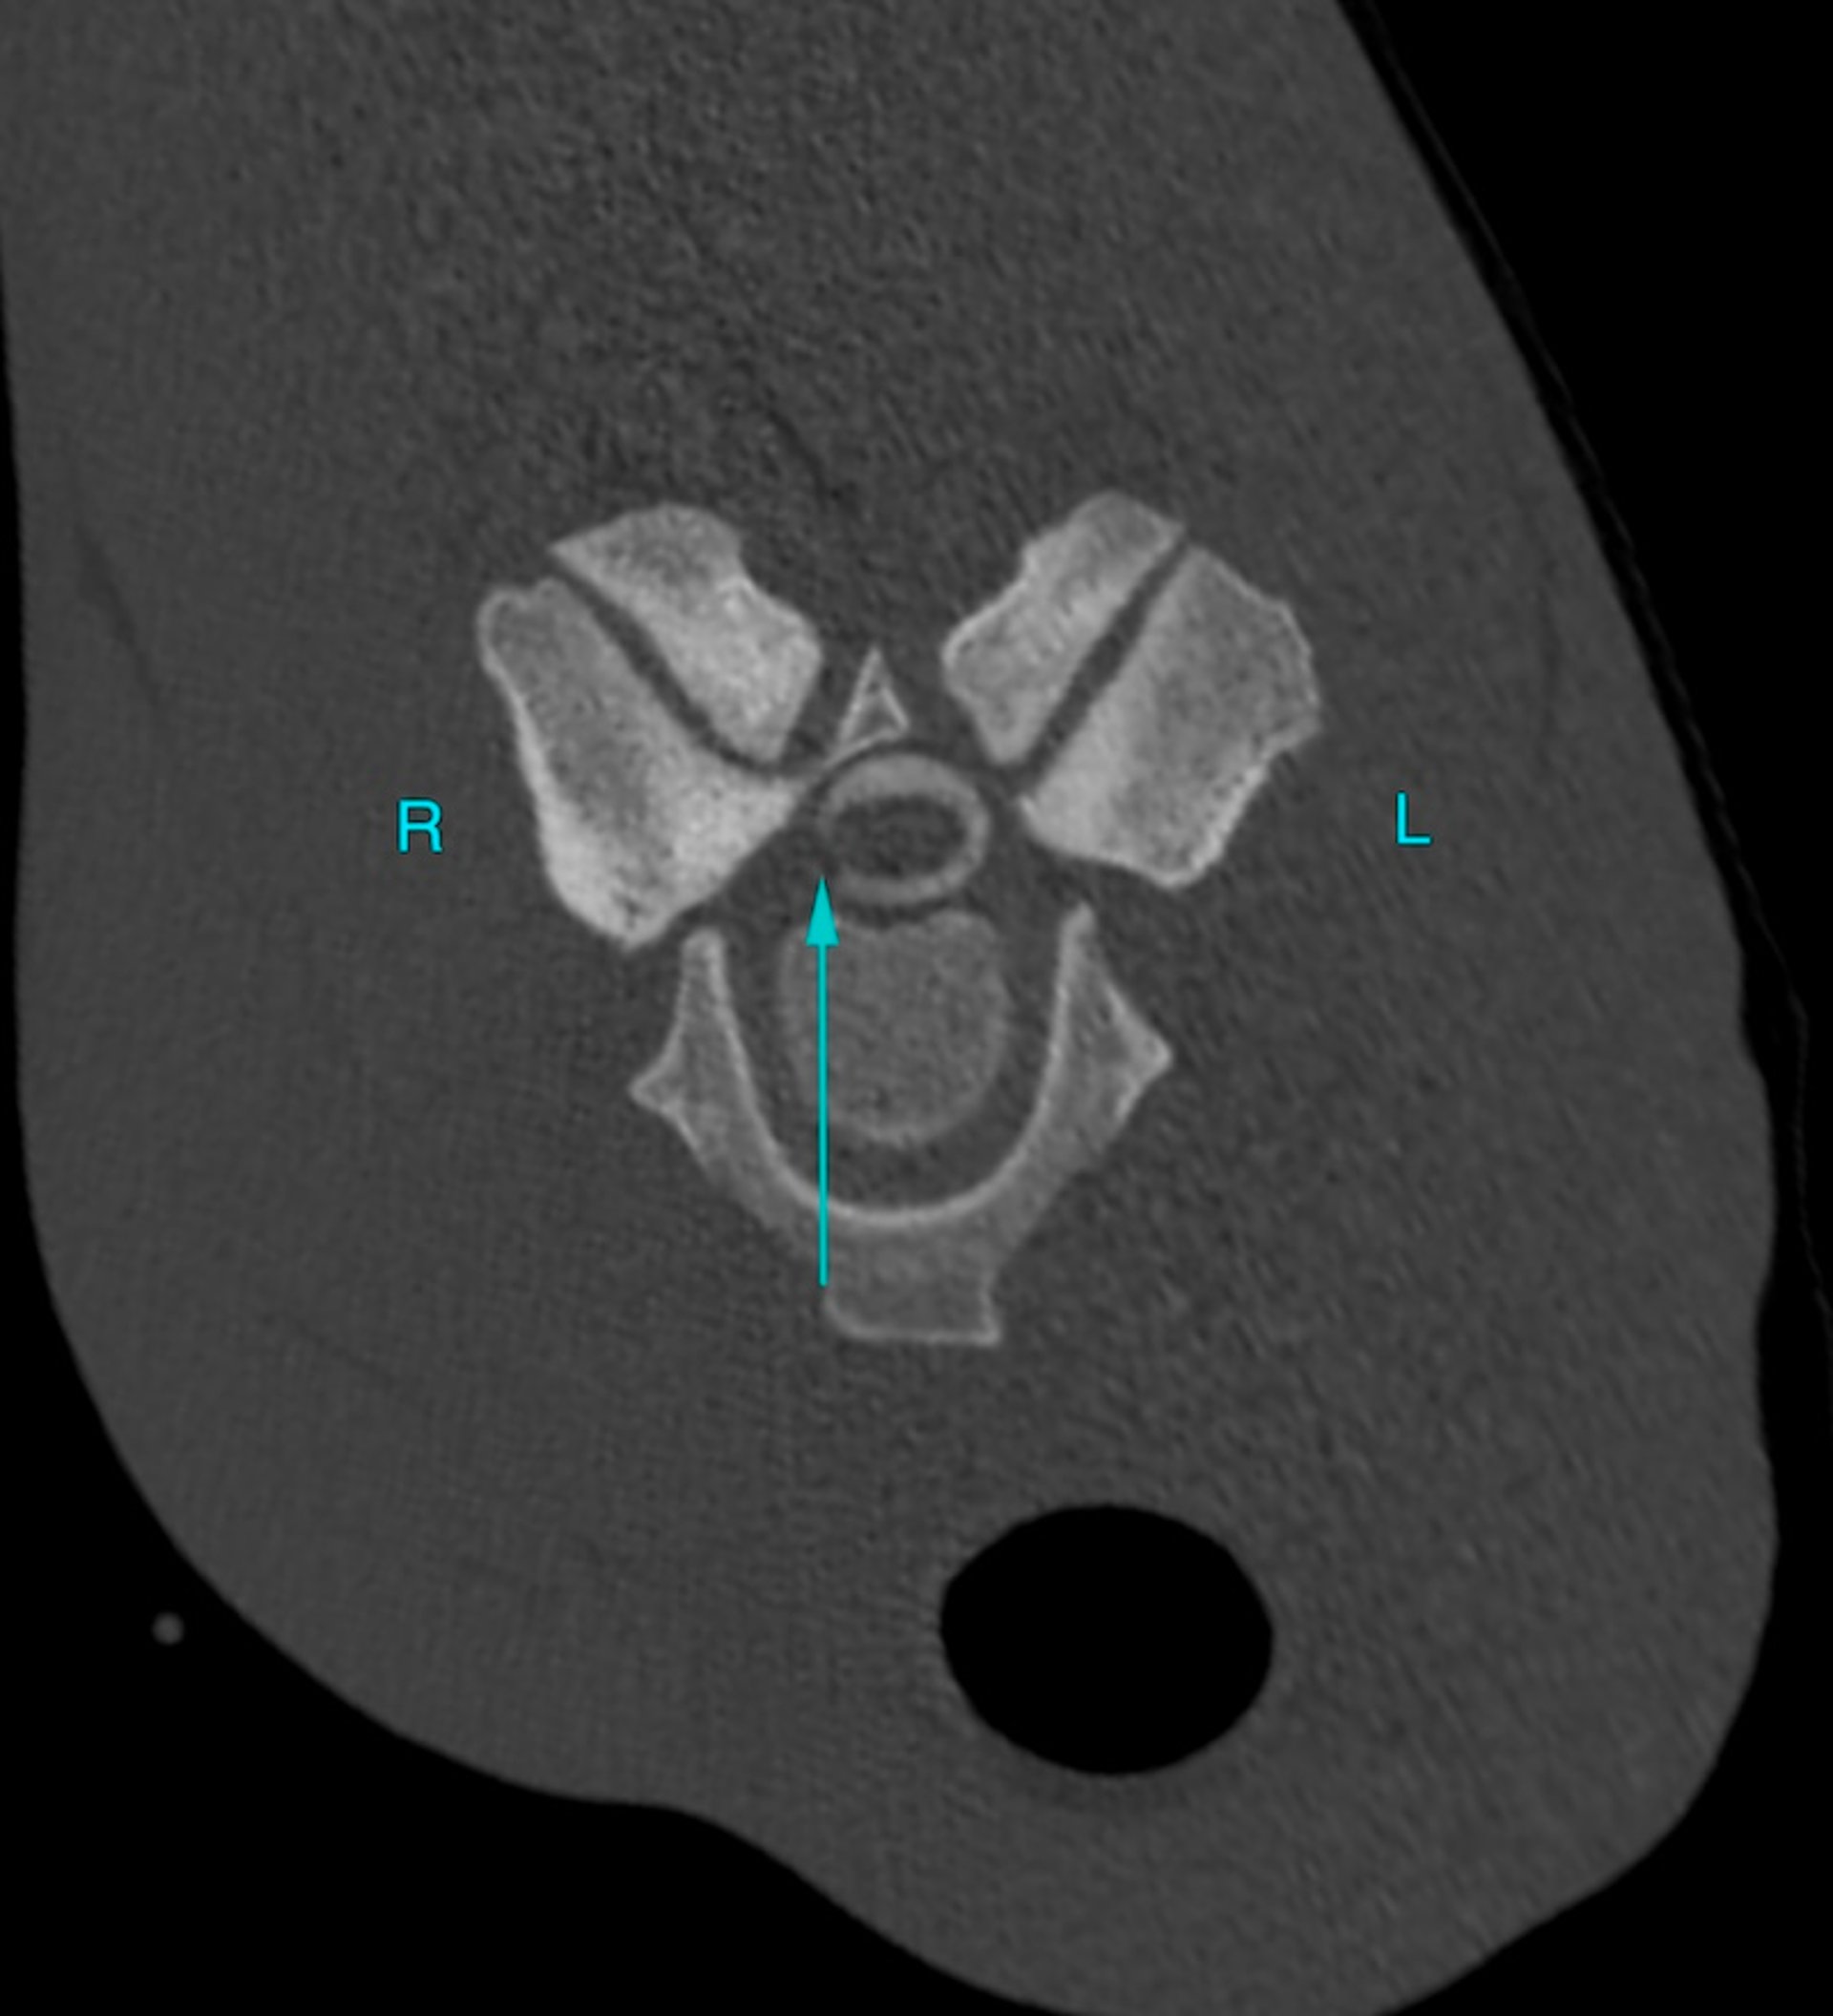

Imagen de TC transversal a nivel de las articulaciones del proceso articular C6-C7 en un caballo, mostrada en una ventana ósea, después de haber inyectado contraste positivo en el espacio subaracnoideo (por ejemplo, mielograma). El lado izquierdo del paciente está a la derecha de la imagen. Se observa una marcada atenuación focal del aspecto lateral derecho de la columna de contraste (flecha) secundaria a osteofitosis/agrandamiento del proceso articular y presunta distensión de la cápsula articular del proceso articular. Esta área de compresión no es detectable en imágenes reconstruidas sagitales y no sería visible en un mielograma radiográfico, dada la ubicación lateral.

Cortesía del Dr. Timothy Manzi.